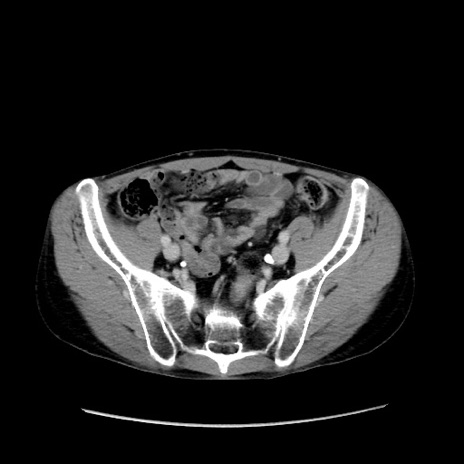

冠状断像